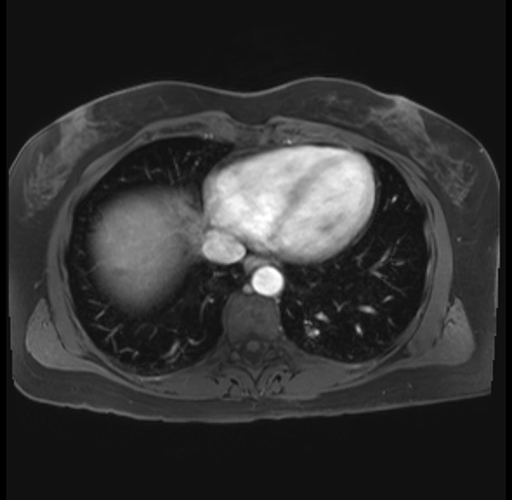

Imaging Analysis

Look through the patient's CT scan to identify any areas of concern for the necessary procedure.

Based on your CT findings, which issue(s) are present and would give reason for "planned slowing down moment(s)" in this case?